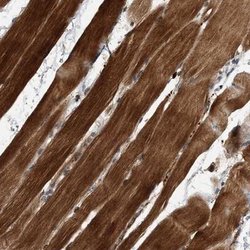

ABIN4355043 IHC

Full details

Method:

Other validation